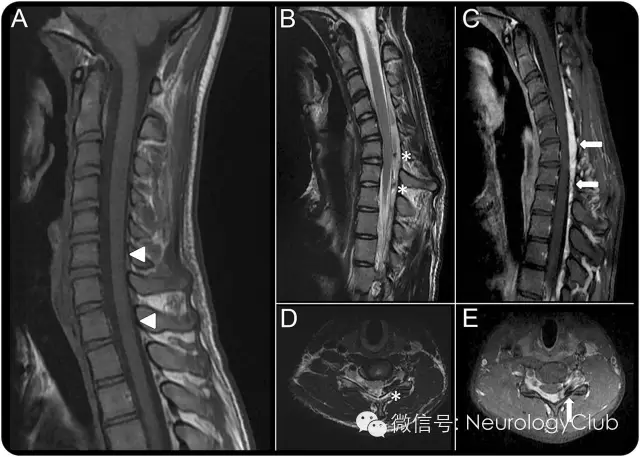

(图2:A:非屈位T1WI提示C7-T1脊髓萎缩;B、D:屈颈位T2WI提示硬膜后腔前移伴颈髓受压;C、E:硬膜外静脉丛充血强化)